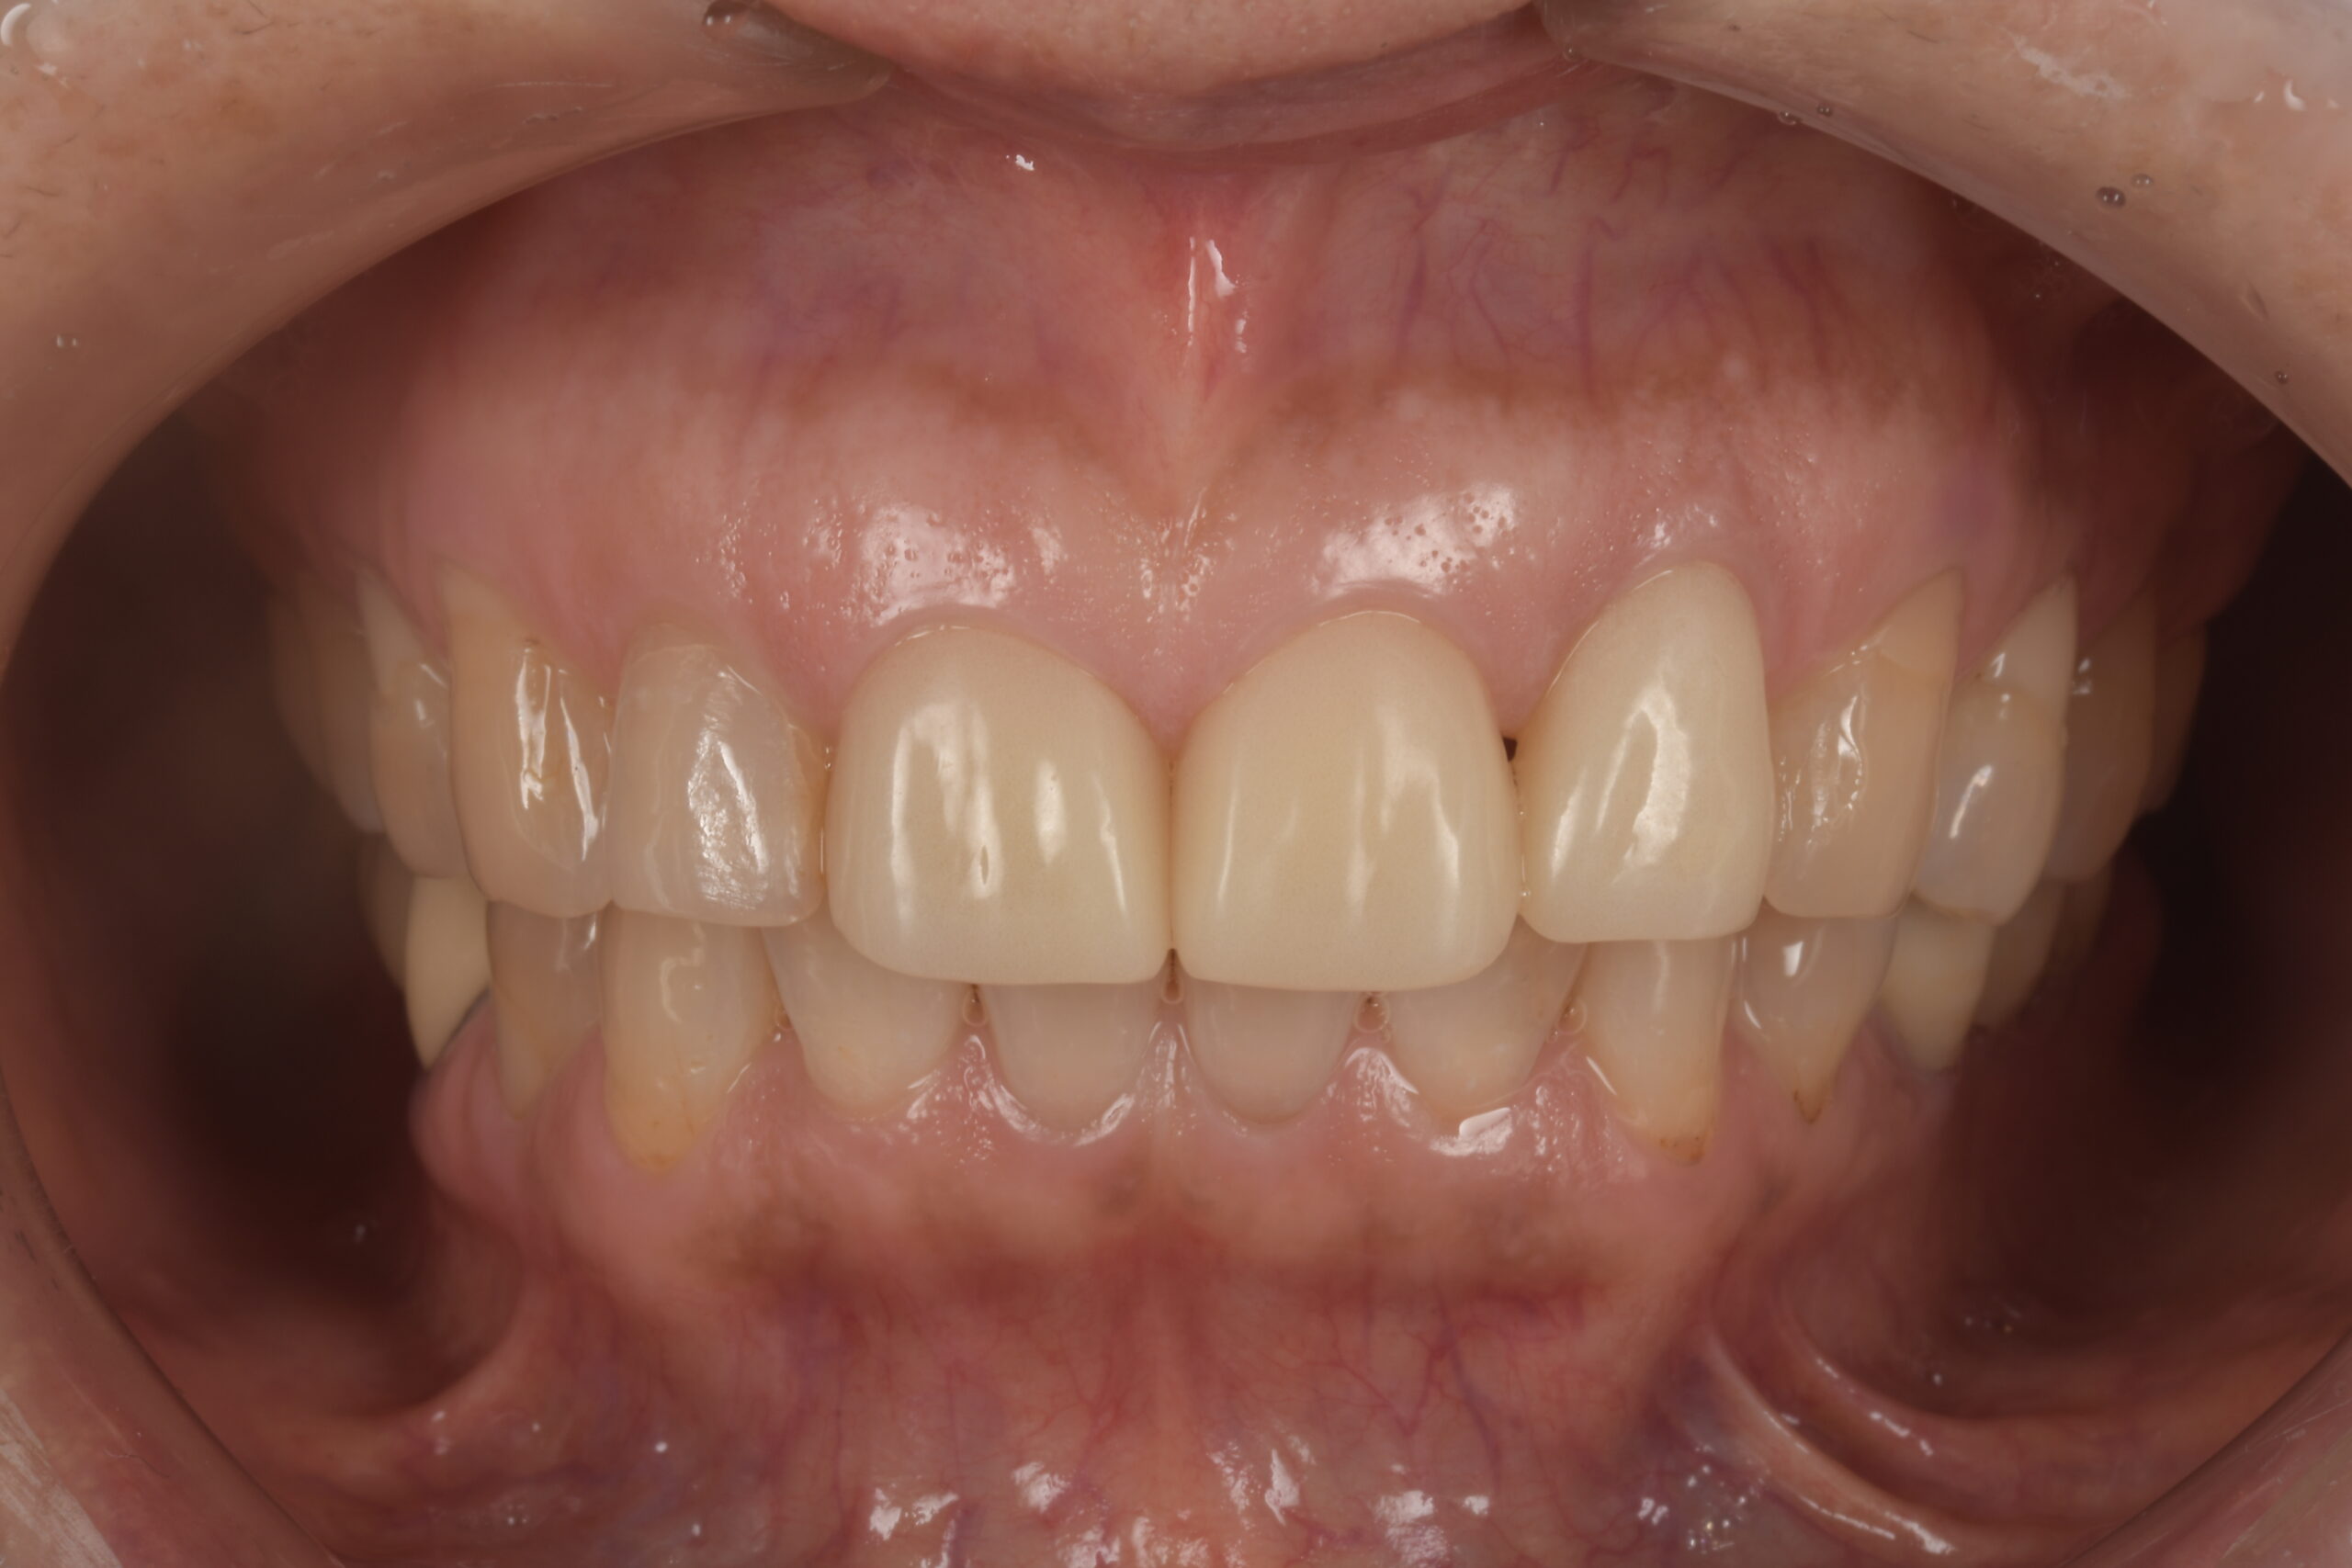

前歯が欠けた(60代)セラミック修復・ホワイトニング

年齢 67歳

性別 女性

初診日 2022年7月

主訴 審美障害

治療内容 セラミック修復・ホワイトニング

治療期間 4ヶ月

治療費用 約50万円

治療経過 前歯が欠けたとのことで来院された。

元々装着されていたラミネートベニアの破折であった。

ラミネートベニアのやり変えに合わせて、左側側切歯のサイズも小さくしたいとのご希望と歯の色も気にされていたため、ホワイトニングをした上で両側中切歯のラミネートベニアはクラウンにて、左側側切歯はラミネートベニアにて修復することとした。

神経にダメージが行かないよう注意深く形成し、仮歯とデジタルデザインにて形態をシミュレーションし、最終補綴物へと移行した。